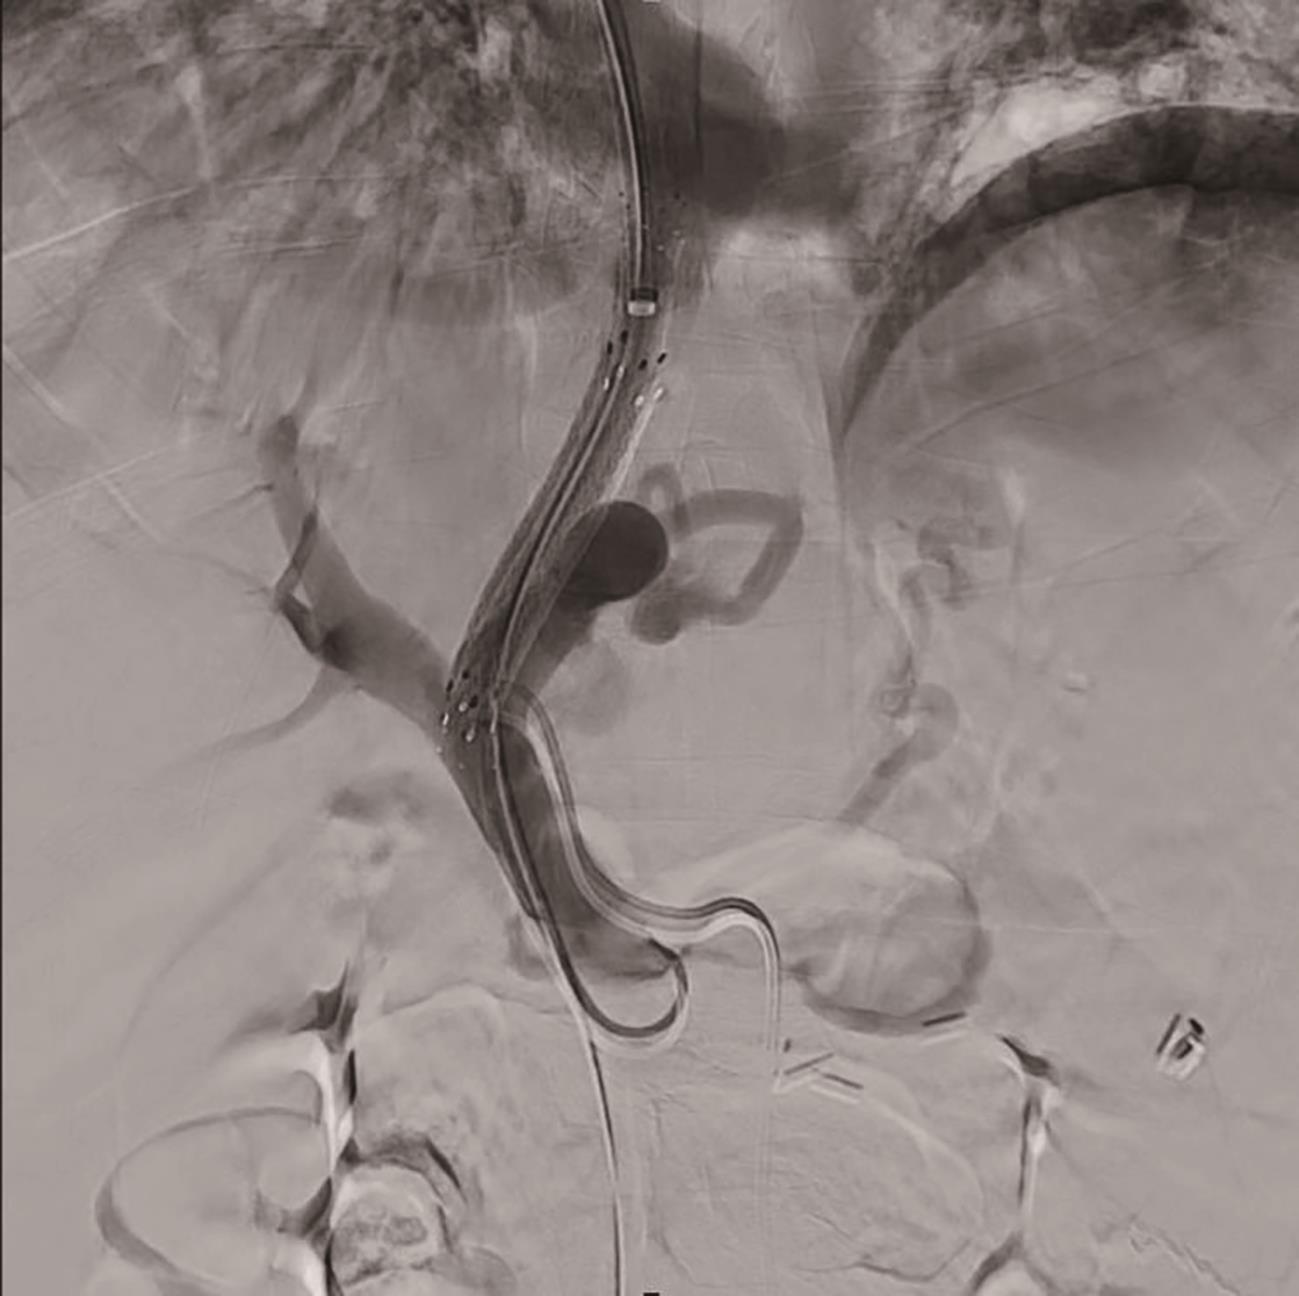

肝硬化食管胃底静脉曲张破裂出血患者经颈静脉肝内门体分流术后非计划再入院的危险因素分析及列线图模型构建

殷芹, 吴兆荣, 张峰, 金春燕, 曹燕平, 肖江强, 诸葛宇征, 王倩

2024, 40(9): 1796-1801. DOI: 10.12449/JCH240913

摘要(1106) HTML (1352) PDF (1108KB)(65)

摘要:

目的  探讨经颈静脉肝内门体分流术(TIPS)的肝硬化食管胃底静脉曲张破裂出血患者出院30 d内发生非计划再入院危险因素,并构建风险预测列线图模型。  方法  选取2020年1月—2023年6月在南京大学医学院附属鼓楼医院因肝硬化食管胃底静脉曲张破裂出血行TIPS的241例患者作为研究对象。分析患者30 d内非计划再入院情况,并依据是否发生非计划再入院分为再入院组(n=36)和未再入院组(n=198)。收集患者临床资料,符合正态分布的计量资料2组间比较采用成组t检验,偏态分布的计量资料2组间比较采Mann-Whitney U检验;计数资料2组间比较采用χ2检验。Logistic回归分析筛选出与非计划再入院相关的独立危险因素。建立列线图预测模型,绘制受试者工作特征曲线(ROC曲线)评估列线图模型预测非计划再入院发生的区分度;绘制校准曲线评估列线图模型预测非计划再入院发生的一致性,采用R语言ResourceSelection包进行Hosmer-Lemeshow评估模型的拟合度,决策曲线分析评估模型的实用性。  结果  年龄(OR=2.664,95%CI:1.139~6.233)、CTP评分(OR=1.655,95%CI:1.098~2.495)、血氨(OR=1.032,95%CI:1.016~1.048)是行TIPS患者出院30 d内非计划再入院的独立危险因素(P值均<0.05)。依据多因素分析结果,构建风险预测列线图模型,通过Bootstrap法重复抽样1 000次展开内部验证,ROC曲线下面积为0.773,高于年龄(0.582)、CTP评分(0.675)、血氨(0.641),校准曲线显示列线图模型预测非计划再入院的概率与实际概率具有较好一致性,Hosmer-Lemeshow显示拟合优度良好(χ2=5.647 3,P=0.686 7)。  结论  年龄、CTP评分和血氨是TIPS术后30 d非计划再入院的独立危险因素,以此建立的列线图预测模型有助于预测行TIPS患者非计划再入院发生风险,为早期预防提供较为准确的决策依据。